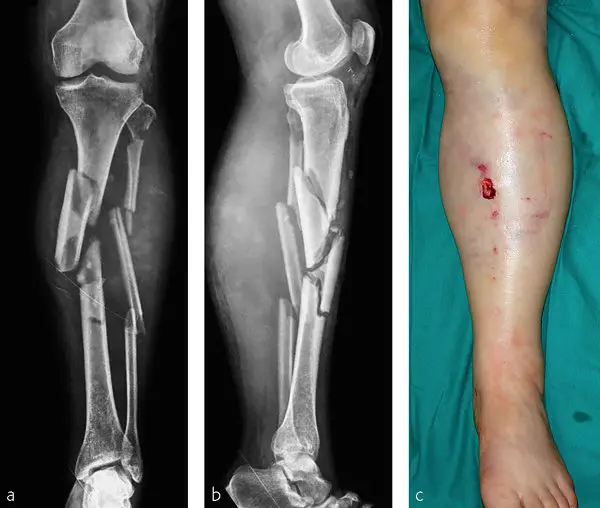

He shared images of a similar fracture to illustrate the treatment process and clarified that the images were not of Vonn’s actual injury.

Morse explained that the device shown was an external fixator, often called an “x-fix.” This apparatus stabilizes fractured bones, particularly the tibia.

It is commonly used in complex leg breaks requiring staged surgical repair. The explanation underscored the long rehabilitation ahead.